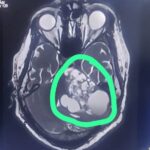

ಮಂಗಳೂರು : ಮಹತ್ವದ ವೈದ್ಯಕೀಯ ಸಾಧನೆಯೊಂದರಲ್ಲಿ ಮುಕ್ಕದಲ್ಲಿರುವ ಶ್ರೀನಿವಾಸ ಆಸ್ಪತ್ರೆಯು 30 ವರ್ಷದ ರೋಗಿಯೊಬ್ಬರಿಗೆ ಜೀವ ಉಳಿಸುವ ಶಸ್ತ್ರಚಿಕಿತ್ಸೆಯನ್ನು ಯಶಸ್ವಿಯಾಗಿ ನಡೆಸಿದ್ದು, ಈ ಹಿಂದೆ ಅವರ ಜೀವಕ್ಕೆ ಗಂಭೀರ ಅಪಾಯವನ್ನುಂಟುಮಾಡಿದ್ದ ಗಮನಾರ್ಹವಾದ ಮೆದುಳಿನ ಗೆಡ್ಡೆಯನ್ನು ತೆಗೆದುಹಾಕಿದೆ.

ಡಾ.ದೀಪಕ್ ಅವರ ರಾಯಚೂರಿನ ಸಹ ವೈದ್ಯಕೀಯ ಶಾಲೆಯ ಬ್ಯಾಚ್ ಮೇಟ್ ಬೆಂಗಳೂರಿನಲ್ಲಿ ಜುಲೈನಲ್ಲಿ ಈ ರೋಗಿಯ ವಿಫಲ ಶಸ್ತ್ರಚಿಕಿತ್ಸೆಯಿಂದ ಹಿನ್ನಡೆಯನ್ನು ಎದುರಿಸಿದ್ದರು, ಅತಿಯಾದ ರಕ್ತಸ್ರಾವದಿಂದ ಕೈಬಿಡಲಾಯಿತು. ಆದಾಗ್ಯೂ, ಶ್ರೀನಿವಾಸ ಆಸ್ಪತ್ರೆ ಮುಕ್ಕದಲ್ಲಿ ಲಭ್ಯವಿರುವ ಸುಧಾರಿತ ವೈದ್ಯಕೀಯ ತಂತ್ರಜ್ಞಾನ ಮತ್ತು ಪರಿಣತಿಯಿಂದಾಗಿ, ರೋಗಿಯ ಸ್ಥಿತಿಯು ಗಮನಾರ್ಹವಾದ ಬದಲಾವಣೆಗೆ ಸಾಕ್ಷಿಯಾಗಿದೆ.

ರಾಯಚೂರಿನ 30 ವರ್ಷದ ಇಬ್ಬರು ಮಕ್ಕಳ ತಂದೆಗೆ ಶ್ರವಣ ದೋಷ, ದೃಷ್ಟಿ ಮಂದವಾಗುವುದು, ತಲೆನೋವು ಮತ್ತು ನಿರಂತರ ವಾಂತಿ ಸೇರಿದಂತೆ ಅವರ ದುರ್ಬಲಗೊಳಿಸುವ ಲಕ್ಷಣಕಾಣಿಸಿತ್ತು.. ಯಶಸ್ವಿ ಶಸ್ತ್ರಚಿಕಿತ್ಸೆ ಈ ಸಮಸ್ಯೆಗಳನ್ನು ಪರಿಹರಿಸಿದೆ. ಹಿಂದಿನ ವಿಫಲ ಶಸ್ತ್ರಚಿಕಿತ್ಸೆಯ ಹೊರತಾಗಿಯೂ, ಬೇರೆಡೆ ಪ್ರಯತ್ನಿಸಿದ ಮತ್ತು ಮುಂದುವರಿದ ಕ್ಷೀಣತೆ, ಶ್ರೀನಿವಾಸ ಆಸ್ಪತ್ರೆ ಮುಕ್ಕದಲ್ಲಿ ನರಶಸ್ತ್ರಚಿಕಿತ್ಸಕ ತಂಡವು ನಡೆಸಿದ ನಿಖರವಾದ ಕಾರ್ಯವಿಧಾನದ ನಂತರ ರೋಗಿಯ ಸ್ಥಿತಿಯು ಉತ್ತಮವಾಗಿ ಸುಧಾರಿಸಿತು.

ಡಾ.ದೀಪಕ್, ಜೊತೆಗೆ ಡಾ.ಪ್ರಶಾಂತ್, ಅನಸ್ತೇಷಿಯಾ ಪ್ರೊಫೆಸರ್ , ಮತ್ತು ಸ್ನಾತಕೋತ್ತರ ಪದವೀಧರರು, ದಾದಿಯರು ಮತ್ತು ಸಹಾಯಕ ಸಿಬ್ಬಂದಿ ರೋಗಿಯನ್ನು ನೋಡಿಕೊಳ್ಳಲು ಅವಿರತವಾಗಿ ಶ್ರಮಿಸಿದರು. ಅತ್ಯಾಧುನಿಕ ಉಪಕರಣಗಳೊಂದಿಗೆ ನಡೆಸಿದ ಶಸ್ತ್ರಚಿಕಿತ್ಸೆಯು ಹೊಸ ನರಗಳ ಕೊರತೆಯನ್ನು ಉಂಟುಮಾಡದೆಯೇ ಗೆಡ್ಡೆಯನ್ನು ಸಂಪೂರ್ಣವಾಗಿ ತೆಗೆದುಹಾಕಲು ಕಾರಣವಾಯಿತು. ಇದು ರೋಗಿಯ ಹಿಂದಿನ ಅಪಸಾಮಾನ್ಯ ಕ್ರಿಯೆಯಲ್ಲಿ ಗಮನಾರ್ಹ ಸುಧಾರಣೆಗೆ ಕಾರಣವಾಯಿತು. ಗೆಡ್ಡೆಯ ಹಾನಿಕರವಲ್ಲದ ಸ್ವಭಾವವು ಸಂಪೂರ್ಣ ಗುಣಪಡಿಸುವಿಕೆಯನ್ನು ಸೂಚಿಸುತ್ತದೆ. ರೋಗಿಯು ಹೊಸ ಮನುಷ್ಯನಾಗಿ ಮನೆಗೆ ಮರಳಲು ಅನುವು ಮಾಡಿದ್ದು, ಅವರು ಮಾರಣಾಂತಿಕ ಸ್ಥಿತಿಯಿಂದ ಮುಕ್ತರಾಗಿದ್ದಾರೆ.